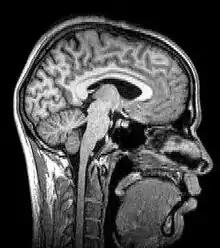

Neuroimagem ou imagem cerebral é o uso de várias técnicas para imagem, direta ou indiretamente, da estrutura, função/farmacologia do sistema nervoso. Essa é uma disciplina relativamente nova dentro da medicina, neurociência e psicologia.[1] Os médicos que se especializam no desempenho e na interpretação da neuroimagem no cenário clínico são denominados neuroradiologistas.

A ressonância magnética (MRI) usa campos magnéticos e ondas de rádio para produzir imagens de duas ou três dimensões de estruturas cerebrais de alta qualidade sem uso de radiação ionizante (raios-X) ou traçadores radioativos.